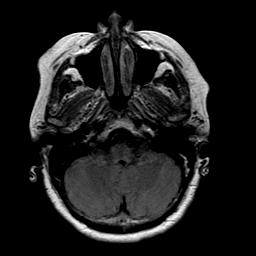

Stroke: proton density-weighted MR #1 -- Slice #4

[Home][Help][Clinical] Slice 4